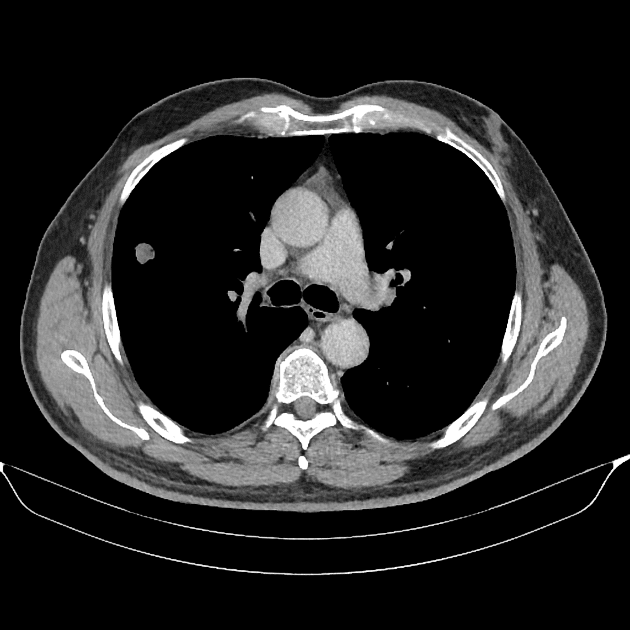

U phổi

» Thông tin: Nam giới – 70 tuổi.

» Lâm sàng: Ho / Tiền sử hút thuốc lá.

# Ung thư biểu mô tuyến (Adenocarcinoma).